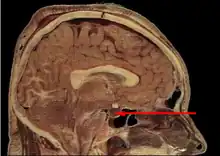

L'hypophyse se trouve dans une cavité osseuse, la fosse hypophysaire qui se situe dans l'os sphénoïde. Elle est protégée par la selle turcique. Elle est reliée à une autre partie du cerveau appelée l'hypothalamus par une tige hypophysaire (également appelée tige pituitaire). Elle produit des hormones qui gèrent une large gamme de fonctions corporelles, dont les hormones trophiques qui stimulent les autres glandes endocrines. Cette fonction lui a valu de se faire appeler par les scientifiques « glande maîtresse » du corps, mais aujourd'hui on sait que l'hypophyse est régulée par les hormones (neuro-hormones) émises par l'hypothalamus.

Anatomie

L'hypophyse est divisée en deux lobes : l'antéhypophyse (adénohypophyse) en avant, et la posthypophyse (neurohypophyse) en arrière. L'adénohypophyse dérive du plafond de la cavité buccale primitive (stomodeum), tandis que la neurohypophyse est une extension de l'hypothalamus, relié à celui-ci par la tige pituitaire, et contient les axones de neurones dont les corps cellulaires se trouvent dans l'hypothalamus. On peut également trouver entre l'antéhypophyse et la posthypophyse, une troisième structure, l'hypophyse intermédiaire, bien développée chez certaines espèces animales[Lesquelles ?] : chez l'humain, l'hypophyse intermédiaire (pars intermedia) est seulement visible en période fœtale et jusqu'à l'âge de dix ou vingt ans ; chez l'adulte, il subsiste quelques structures kystiques (follicules, restes de la poche de Rathke), ainsi qu'un infiltrat chromatophile basophile.

La posthypophyse se forme à partir d'une projection du plancher du diencéphale, qui donnera l'hypothalamus et la posthypophyse, reliés par la tige pituitaire. Cette ébauche tend à se rapprocher de l'ébauche de l'antéhypophyse, puis fusionne avec elle durant la période fœtale.